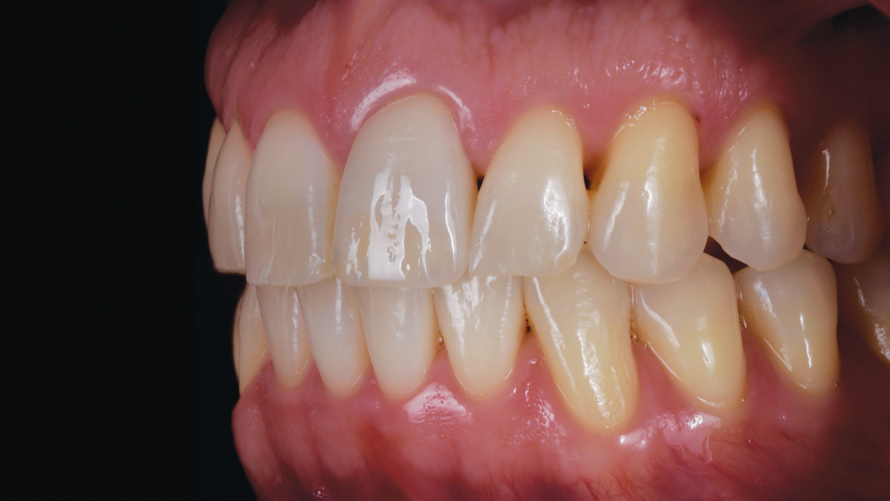

Two patients presented separately to the clinic for the elective replacement of an asymptomatic, discolored, full-coverage restoration on a single maxillary central incisor. The chief complaints of each patient were based solely on esthetics (Figure 1 and Figure 2). During the intraoral examination of each tooth, both patients demonstrated an unremarkable occlusion, good oral hygiene, firm gingiva, probing depths of 2 mm to 3 mm, no bleeding within the sulcus, and tooth mobility that was within normal limits. The results of all sensitivity tests, which included cold, percussion, and palpation, were negative.

(2.) Case 2: Patient presentation of an asymptomatic, unesthetic full-coverage ceramic restoration on the maxillary left central incisor.

Figure 2